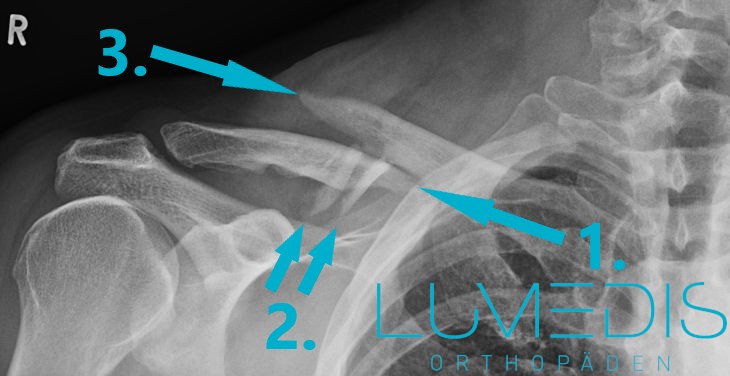

Röntgenbild eines Schlüsselbeinbruchs (a.p.):

Die Anfertigung eines Röntgenbildes ist für die Diagnosestellung eines Schlüsselbeinbruchs essentiell.

Hier können die knöchernen Strukturen genau beurteilt und das Ausmaß der Verletzung eingeschätzt und klassifiziert werden.

Die Röntgen-Untersuchung erfolgt stets in zwei Ebenen, damit nichts übersehen werden kann.

Um mögliche Begleitverletzungen auszuschließen oder abzugrenzen sollte die Röntgenaufnahme auch immer das Schultereckgelenk, also die Gelenkverbindung zwischen Schlüsselbein und Schulterblatt, miteinschließen.

Schlüsselbeinbruch mit zwei freien Knochenfragmenten